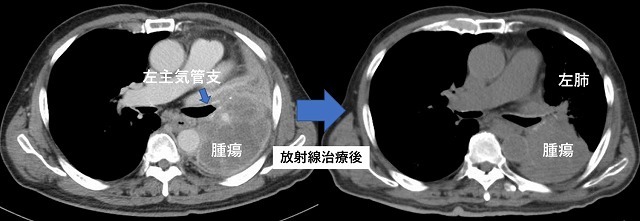

肺がん

腫瘍により左主気管支が閉塞。

左肺が完全無気肺(含気がない状態)となり呼吸苦が強い。

放射線治療により左主気管支の閉塞が解除され呼吸苦が改善。